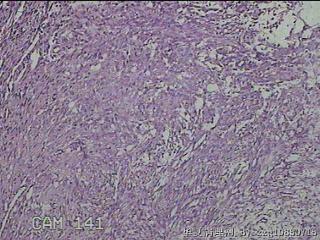

左肘部包块

性别

男

年龄

39

临床诊断

左肘部肿物:炎性脂肪瘤

一般病史

发现左肘部肿物1周。

标本名称

大体所见

灰白粉红色组织2x1.8x0.3㎝一团,表面结节状,光滑,切面灰白粉红色,质软。

图4

纤维组织细胞瘤

有外伤史吗,考虑结节性筋膜炎。

首先考虑结节性筋膜炎。

梭形细胞肿瘤,待免疫组化